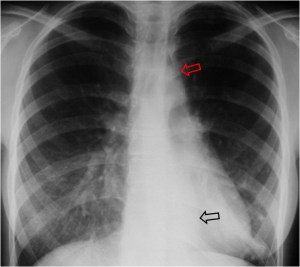

SIGNO DEL DOBLE CONTORNO

Signo de crecimiento de la aurícula izquierda en la radiografía posteroanterior de tórax. La aurícula izquierda no forma parte normalmente del contorno cardiaco derecho en esta proyección; sin embargo, cuando aumenta de tamaño, produce un segundo contorno (flecha negra), además del de la aurícula derecha (flecha blanca).

La radiografía muestra este signo en un enfermo mitral, así como el aumento de tamaño de la silueta cardiaca.